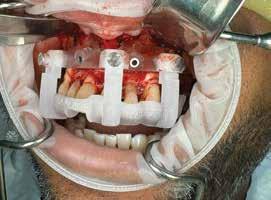

L-Q

LEGALLY MINE

LUMADENT INC.

MANGO VOICE

MEDILOUPES

MEDIT

MEDS 2U PHARMACY: EMERGENCY

DENTAL KITS